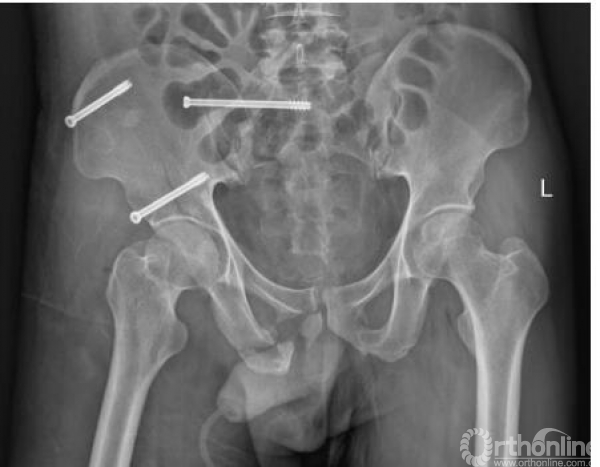

术后复查影像(2017.09.28、2017.10.05)

术后x线(2017.09.17)

骨盆正位、骨盆入口位、骨盆出口位